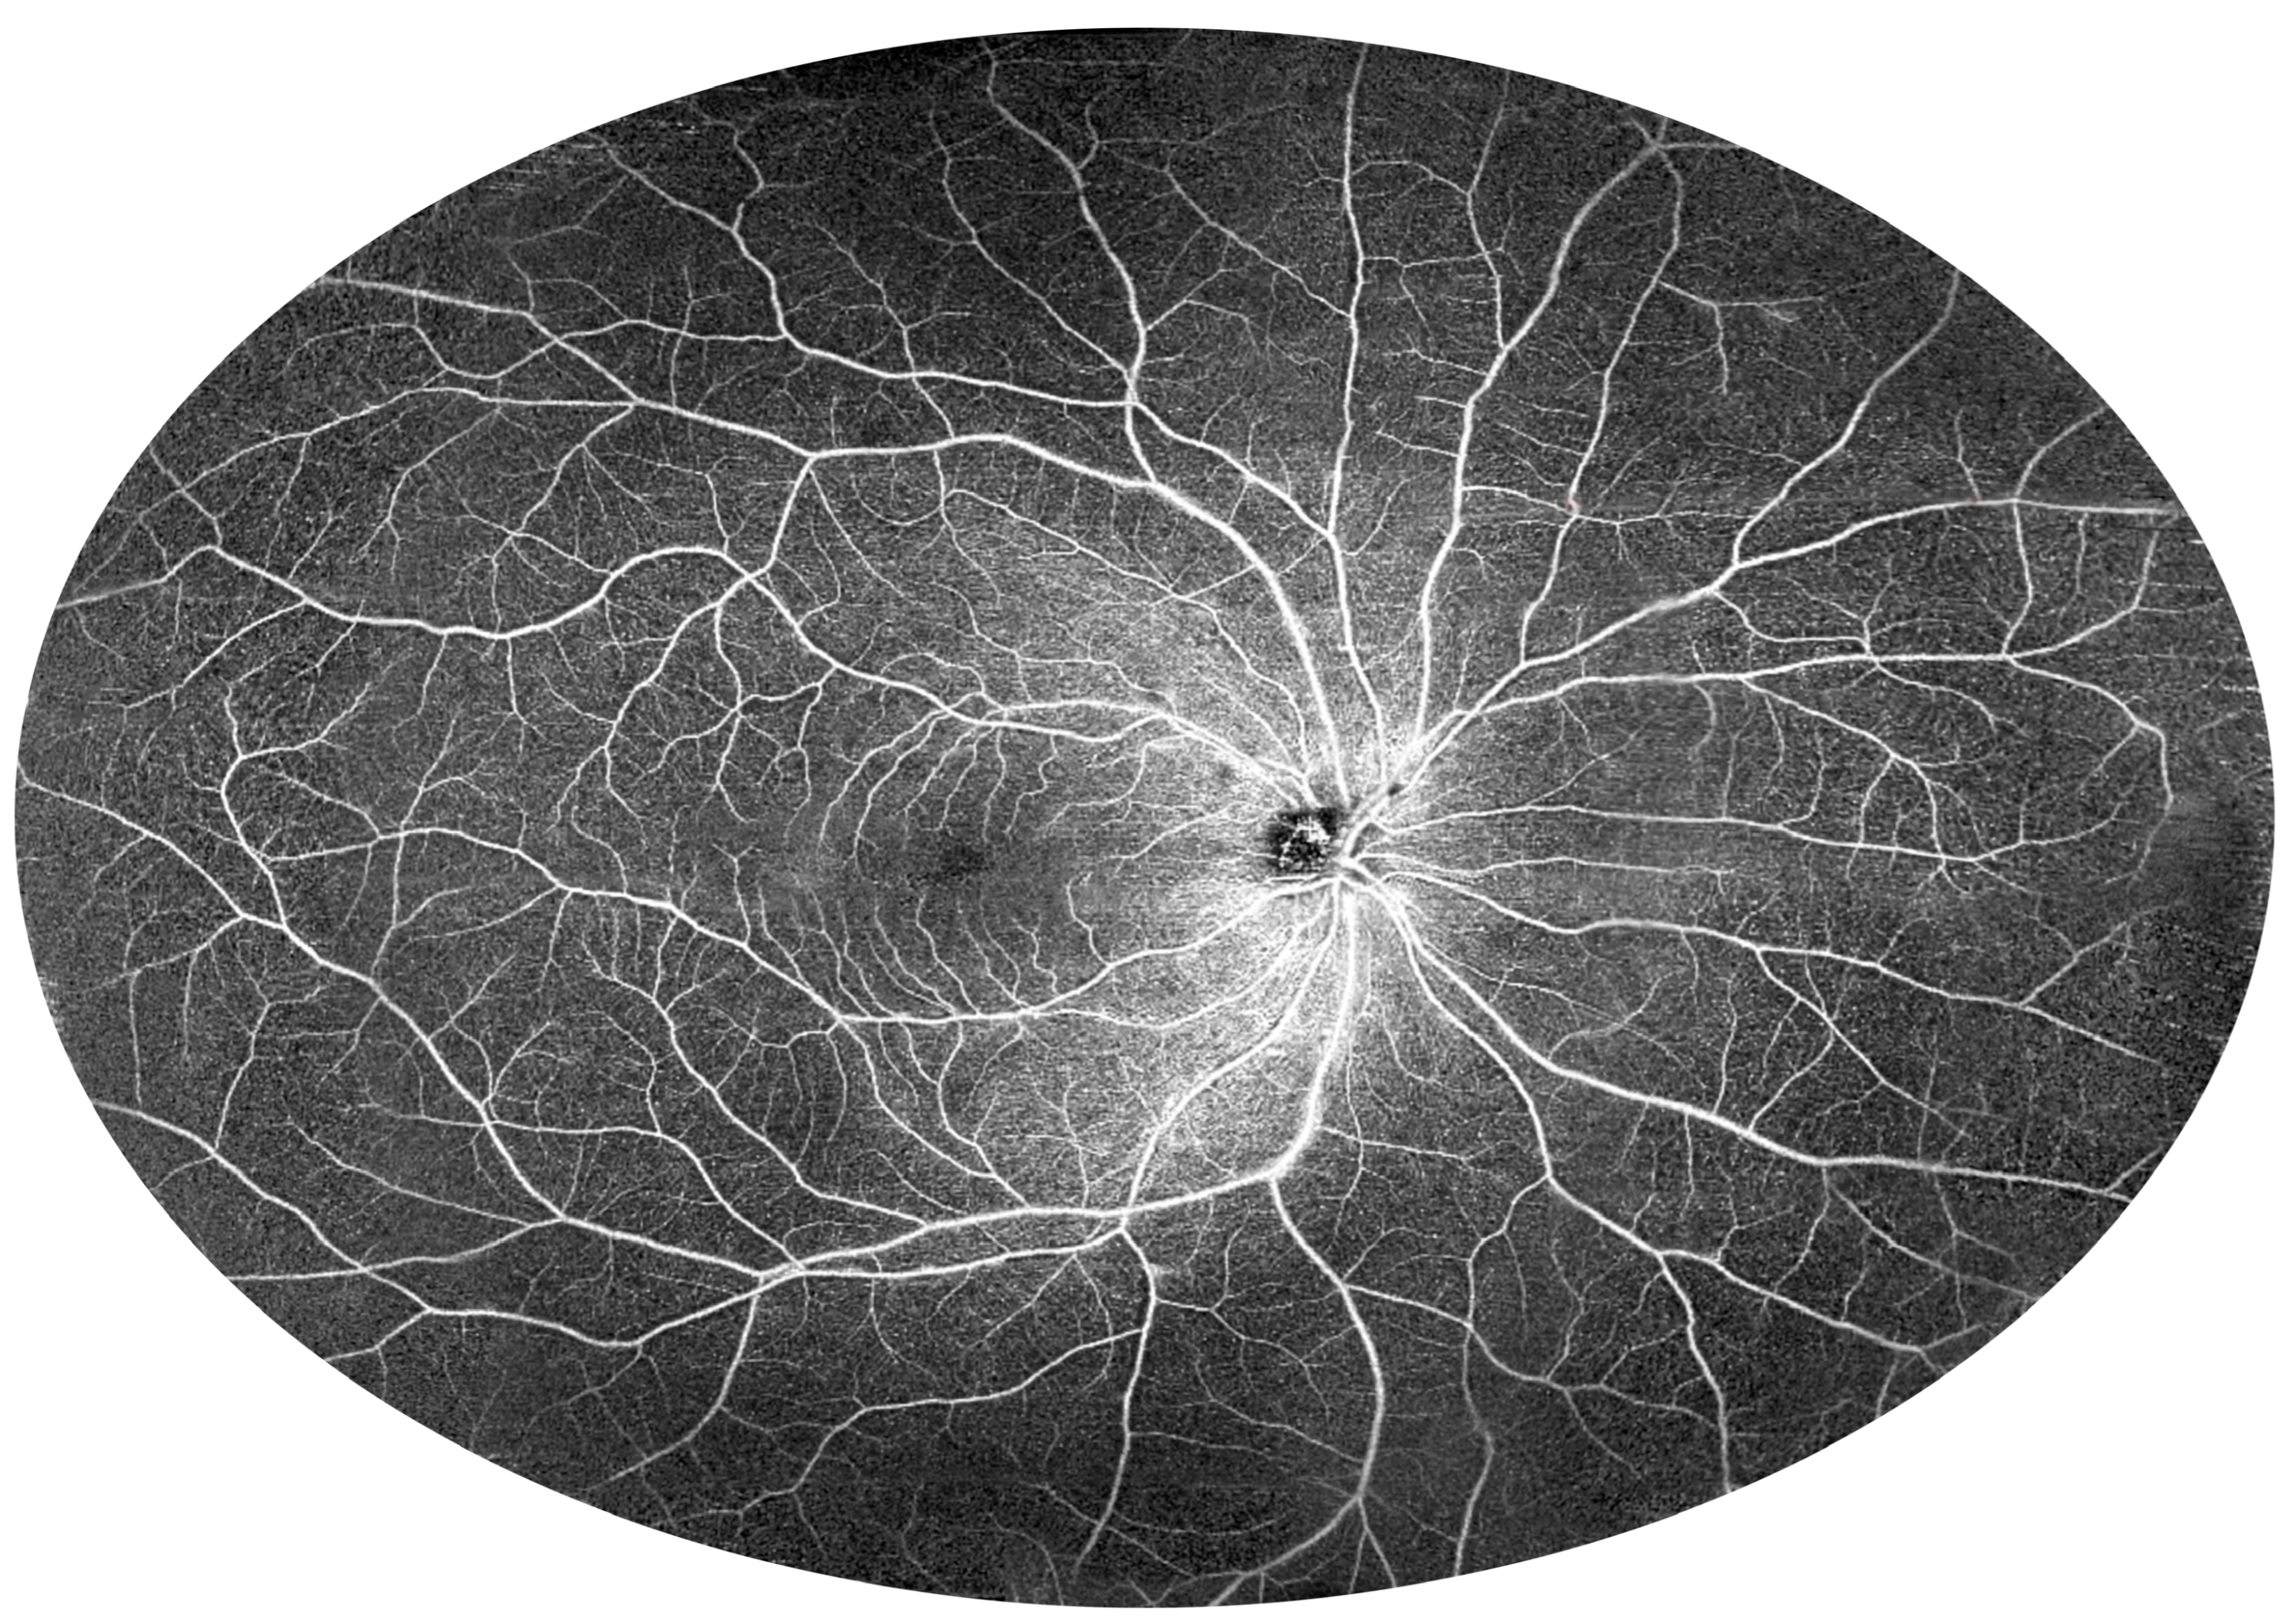

3.2. Angio-OCT Measurements

3.4. UWF Angio-OCT Mosaics